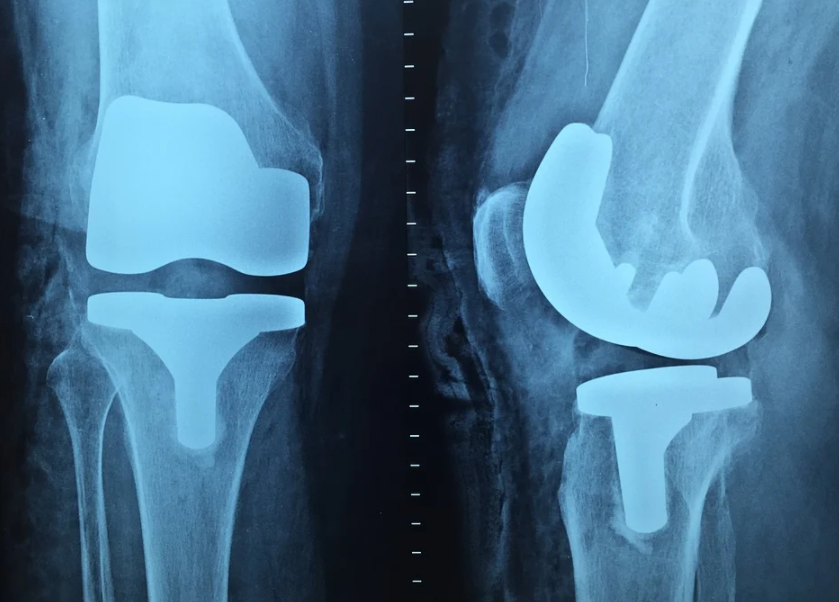

무릎 인공관절수술은 손상된 관절을 제거하고 인공재질로 된 관절로 치환해주는 수술로, 의학 기술 발달과 인공 삽입물의 발달로 과거에 비해 수술 만족도가 크게 개선되었으며, 무릎 관절의 운동범위도 건강한 사람의 운동 범위에 많이 접근해 있는 상태입니다. 건강한 사람의 무릎 관절 운동범위는 약 140도 정도로, 무릎 인공관절수술을 한 사람은 120~130도 정도의 운동범위를 보입니다.

수술과정은 환자 무릎부위를 절개하고 통증의 원인이 되는 손상된 뼈와 연골을 제거한 후 특수합금과 세라믹으로 제작된 인공관절을 끼워넣는 순서로 진행됩니다. 이후 상처를 봉합하고 드레싱하면 수술은 종료가 됩니다. 수술 소요 시간은 총 1~1.5시간 수준이지만, 전후처리 및 회복시간 까지 고려하면 3~4시간 정도의 시간이 소요될 수 있습니다.